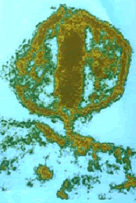

¿Sabes cómo prevenir el Sida?

Temas como ¿qué es el Sida?; vías de transmisión; contagio por vía sexual, sanguínea o perinatal; etapas de la enfermedad; glosario de términos; mitos; condón masculino y femenino y sexo oral son abordadas de manera directa, amena y atractivamente ilustradas. En próximas fechas se dará a conocer el manual en otras facultades de la UV. Así es que si estás interesado en adquirirlo, acude al módulo de consulta externa del Cenati, sito en la Unidad de Ciencias de la Salud (Xalapa), teléfono (012) 815-3598, extensión 122.